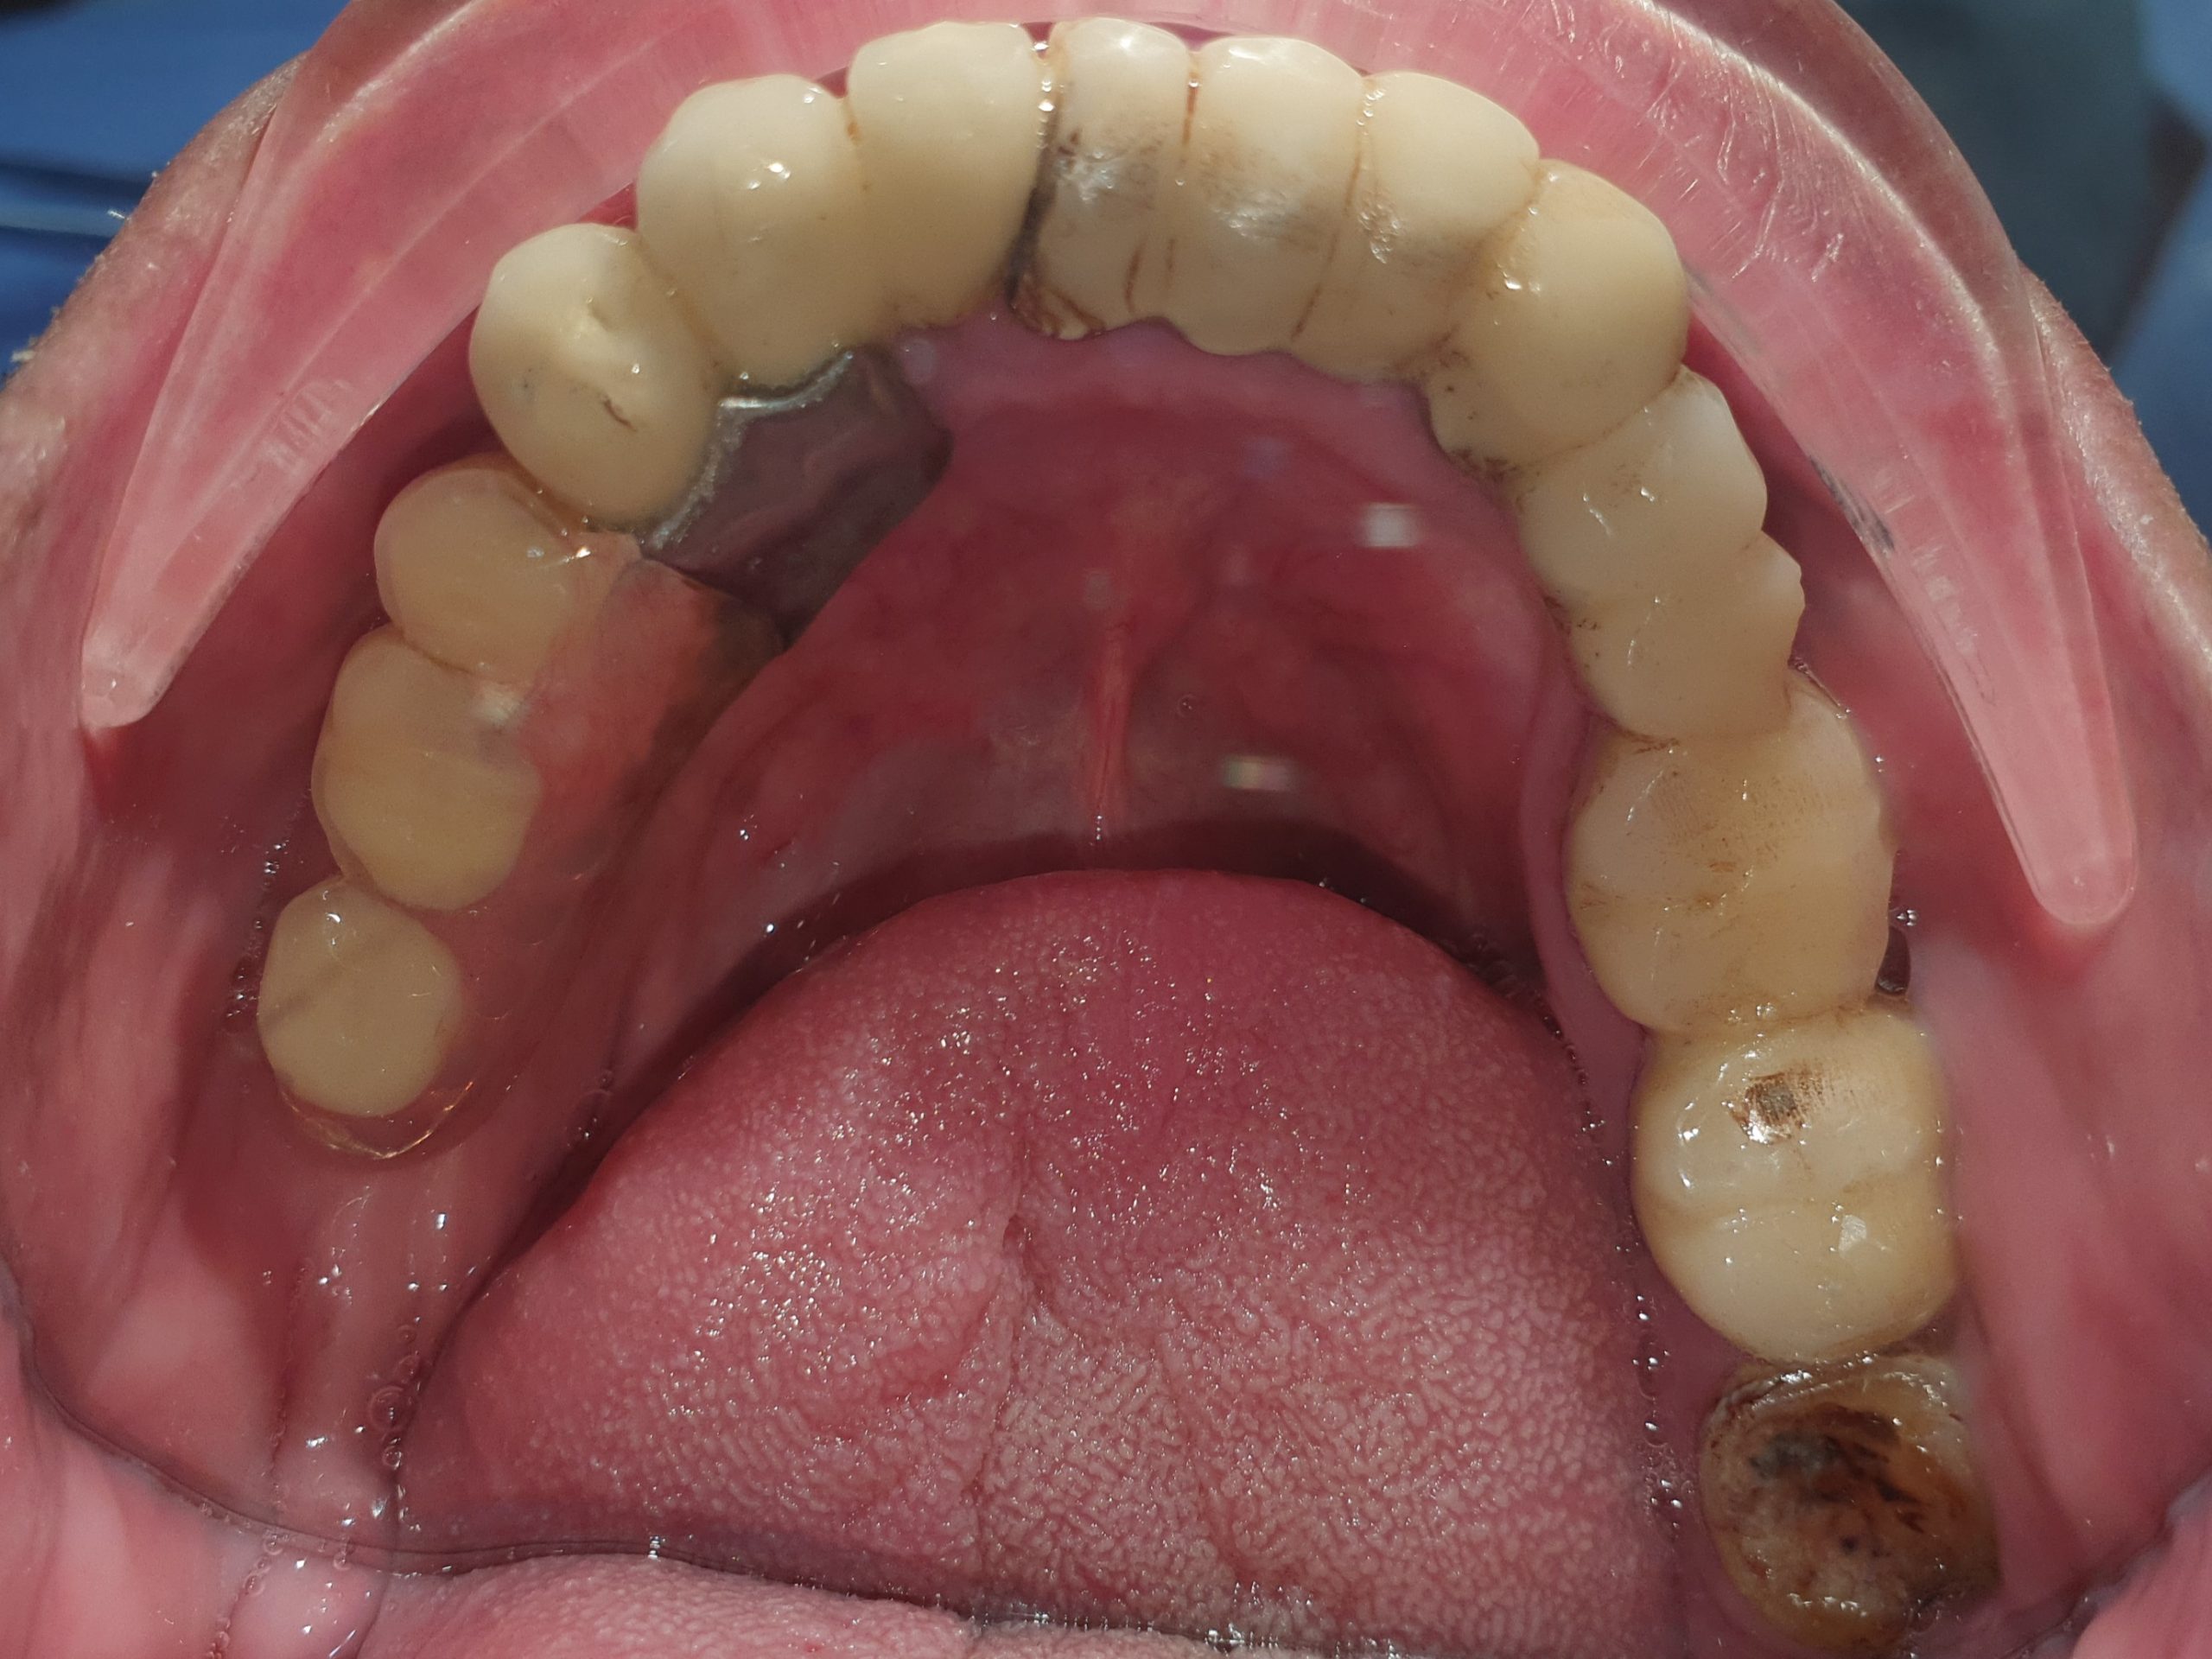

👉Qua thăm khám thấy:

– Bị mất kích thước dọc, cắn sâu. Khớp cắn rất nhạy cảm với thay đổi, dù là rất nhỏ.

– Răng sứ hiện tại quá to, và thô, làm dính liền tất cả các răng sứ với nhau, rất khó vệ sinh, dẫn đến viêm nướu nặng.

– Răng thật còn lại thì mòn cổ nặng, có răng nhiễm trùng cần điều trị tủy

-….

Tình trạng răng ban đầu

Hình ảnh răng hàm trên và dưới